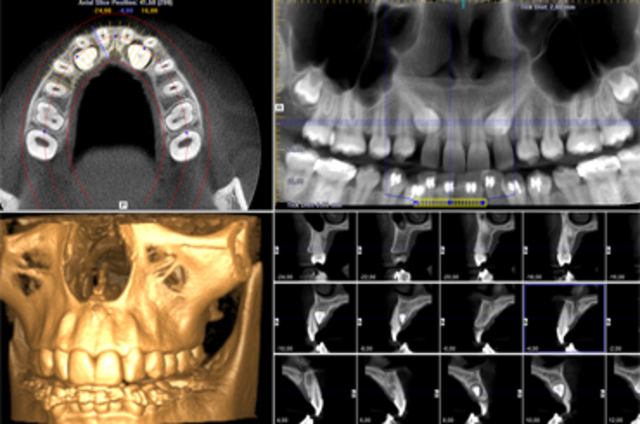

• Primer Prototipo de la Tomografía computarizada de de haz cónico por Dentscan (TCHC)

Primer Prototipo de la Tomografía computarizada de de haz cónico por Dentscan (TCHC)

Se comienzan a lanzar prototipos los cuales aun no eran utilizados solo eran modelos de prueba

• TCHC  de 3/D Dental

TCHC de 3/D Dental

Antes de que mas marcas lanzaran sus prototipos de TCHC. 3/D dental lanza el suyo

• TCHC de Sim/Plant

TCHC de Sim/Plant

Sim/plant Usa las imagenes obtenidas por medio de la tomografia para poder diseñar implantes

• Se comienza a utilizar la TCHC en Europa

Se comienza a utilizar la TCHC en Europa

Despues de un largo tiempo las TCHC se comienzan a utilizar en personas en Europa